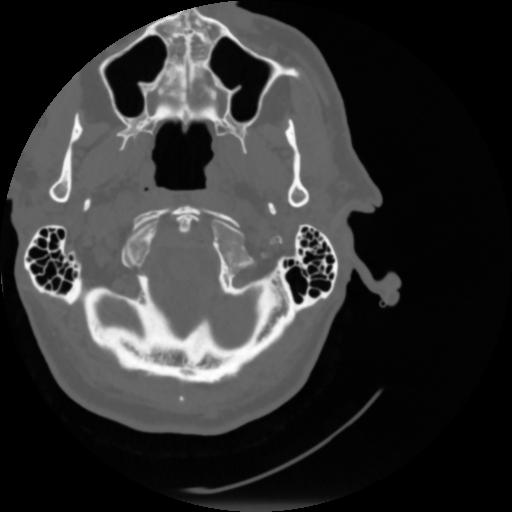

4 CEREBRO,,Vol,0.5,CEREBRO,,